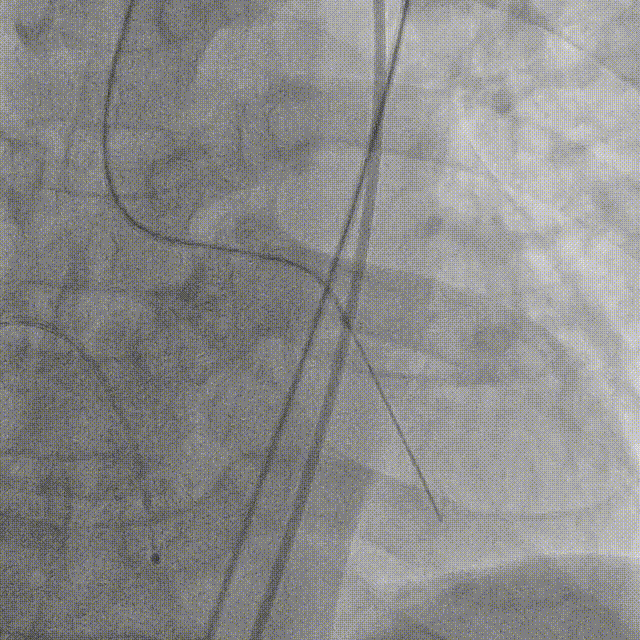

4.导丝跨瓣

直头导丝顺利跨瓣